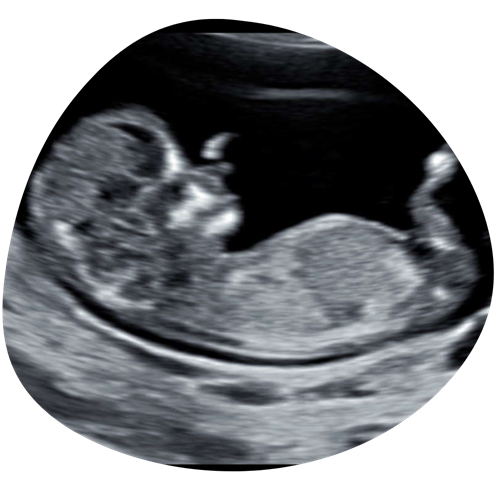

Geslachtsbepaling

Vanaf 14 weken zwangerschap kunnen we het geslacht van je kindje bepalen. Een volle blaas zorgt ervoor dat ze gaan liggen, hierdoor is het geslacht beter in beeld te brengen en krijgen we de mooiste echo beelden van je kindje

€35 (15 minuten)